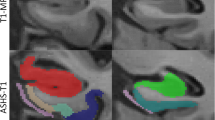

First, hippocampal sections were manually segmented by a trained investigator (SA) into individual subfields in the hematoxylin channel, blinded to density of tau immunoreactivity and clinical group, in the QuPath software using anatomically defined boundaries [1] as described previously [10]. Briefly, hippocampal subfields of interest segmented included dentate gyrus (DG); cornu ammonis (CA) subfields CA4, CA3, CA2, and CA1; subiculum; and entorhinal cortex (ERC) based on the cytoarchitectural features of the layers and anatomical landmarks [12, 24]. The general features used for the segmentations were as follow: DG segmentation represented the granular layer of dentate gyrus. CA4 segmentation was limited to pyramidal cells within the concavity of the DG. CA3 segmentation corresponded to the pyramidal neurons of CA3. CA2 was distinguished from CA3 neurons by higher density of large oval neuronal cells of CA2 pyramidal layer. CA1 subfield was confined to scattered triangular pyramidal cells. For the subiculum, the segmentation started where the stratum radiatum layer of CA1 dissipates and ended where the dark maculated cluster of neurons of the pre-subiculum merge and form a layer (pro-subiculum and subiculum proper). The ERC segmentation consisted of entorhinal cortex, identified by the presence of large island of neurons of layer II, the lamina dissecans of layer IV, and the diagonally oriented cortex of the transentorhinal area (due to the specificity of this cytoarchitectural definition of ERC, we had 40% of cases with available ERC segmentation). Individual subfields which were obscured by significant ripped or damaged tissues, precluding accurate manual segmentation, were excluded from analysis. Figure 1a depicts an AT8 stained hippocampal section of a case with ADNC pathology and representative segmentations of the ROIs investigated in this study. Cortical regions were sampled using a modified belt-transect unbiased method to select representative cortex, as described [25]. The belt-transect method is a reliable procedure for neuropathologic sampling of cortical regions of human brain [4]. In this method the parallel oriented cortex from the sulcal wall is selected for sampling to avoid bias from segmenting areas of the tissue where cortical layers are over or under-represented. This is imperative to reduce bias in digital measurements due to the laminar distribution of tau pathology in AD [42]. Here, a modified belt transect method was used for sampling cortical regions, whereby a trained investigator (SA) used the line tool in QuPath to manually generate two semi-parallel lines to define grey-white matter and pia matter-CSF boundaries of the longest parallel oriented cortex in each section. Next, a script in QuPath creates semi-perpendicular lines in intervals of 250 µm to join the user generated lines to measure the width between these two lines. The program then defines the lateral vertical limits of the ROI at each end where the width of grey matter increases by 0.2 mm. To further reduce bias, we use the create tiles tool to generate 175 µm tiles (Online Resource 1, Supplementary Fig. 1a) in this ROI and a custom script randomly selects a subset of 30% of the tiles for analysis. The final grey matter %AO measurement from each slide image is derived from the average %AO measurement from each random tile per cortical section. In an attempt to further validate our sampling method in this study, we performed alternative sampling using manual segmentation of grey matter with a manual belt-transect method without random tiling and found reliable correlations between the measurements from the two sampling methods (Online Resource 1, Supplementary Fig. 1b, c) and were able to recapitulate our main findings of the study (Online Resource 1, Supplementary Fig. 1d, e).

Hippocampal subfields segmentation and digital histology detection overlay, a Segmentation of hippocampal subregions of an AD case stained with AT8; DG: yellow, CA4: pink, CA3: black, CA2: blue, CA1: red, Subiculum: orange, ERC: green. b Original image and digital histology detection overlay shown in CA1 region for AT8, TauC3, and MN423; red: positive, purple: negative

Next, we used the QuPath program pixel classifier tool with empirically derived positive pixel classifiers for each immunostaining batch of sections as previously validated [19] to calculate the percentage of DAB-positive pixels (%AO) for tau immunoreactivity in each subfield of each image (Fig. 1b). The detailed information and parameters used for positive pixel classifiers and RGB optical density (OD) values for each staining run is provided in Online Resource 1, Supplementary Table 1. Staining batches were performed largely by region and included samples from both clinical groups to reduce batch effects in our main outcomes comparing aAD and naAD groups. For each staining batch, stain RGB OD values were derived empirically from the average value from random tau-positive pathology across five randomly selected images. Stain RGB OD values were used for detecting DAB stain and thresholding based on the minimum OD of positive stain to differentiate pathology signal from background noise. Next, the positive pixel detection algorithms were created for each staining batch based on stain RGB values. An example of digital overlay of positive pixel detection for each staining run is depicted Online Resource 1, Supplementary Fig. 2.